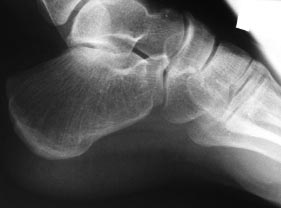

Спасибо всем, кто принимает участие в обсуждении случая. Досылаю рентгенограммы и МРТ. Хотелось-бы уточнить объем резекции пяточных костей.

Имя     : R-ЗЕО - РСФПЮОБС ЛПУФШ МЕЧБС.jpg

Тип     : image/jpg

Размер  : 25939 байтов

Url     : http://weborto.net:8080/pipermail/ortho/attachments/20120619/3904cc51/attachment-0003.jpg

Имя     : R-ЗЕО - РСФПЮОБС ЛПУФШ РТБЧБС.jpg

Размер  : 24894 байтов

Url     : http://weborto.net:8080/pipermail/ortho/attachments/20120619/3904cc51/attachment-0004.jpg